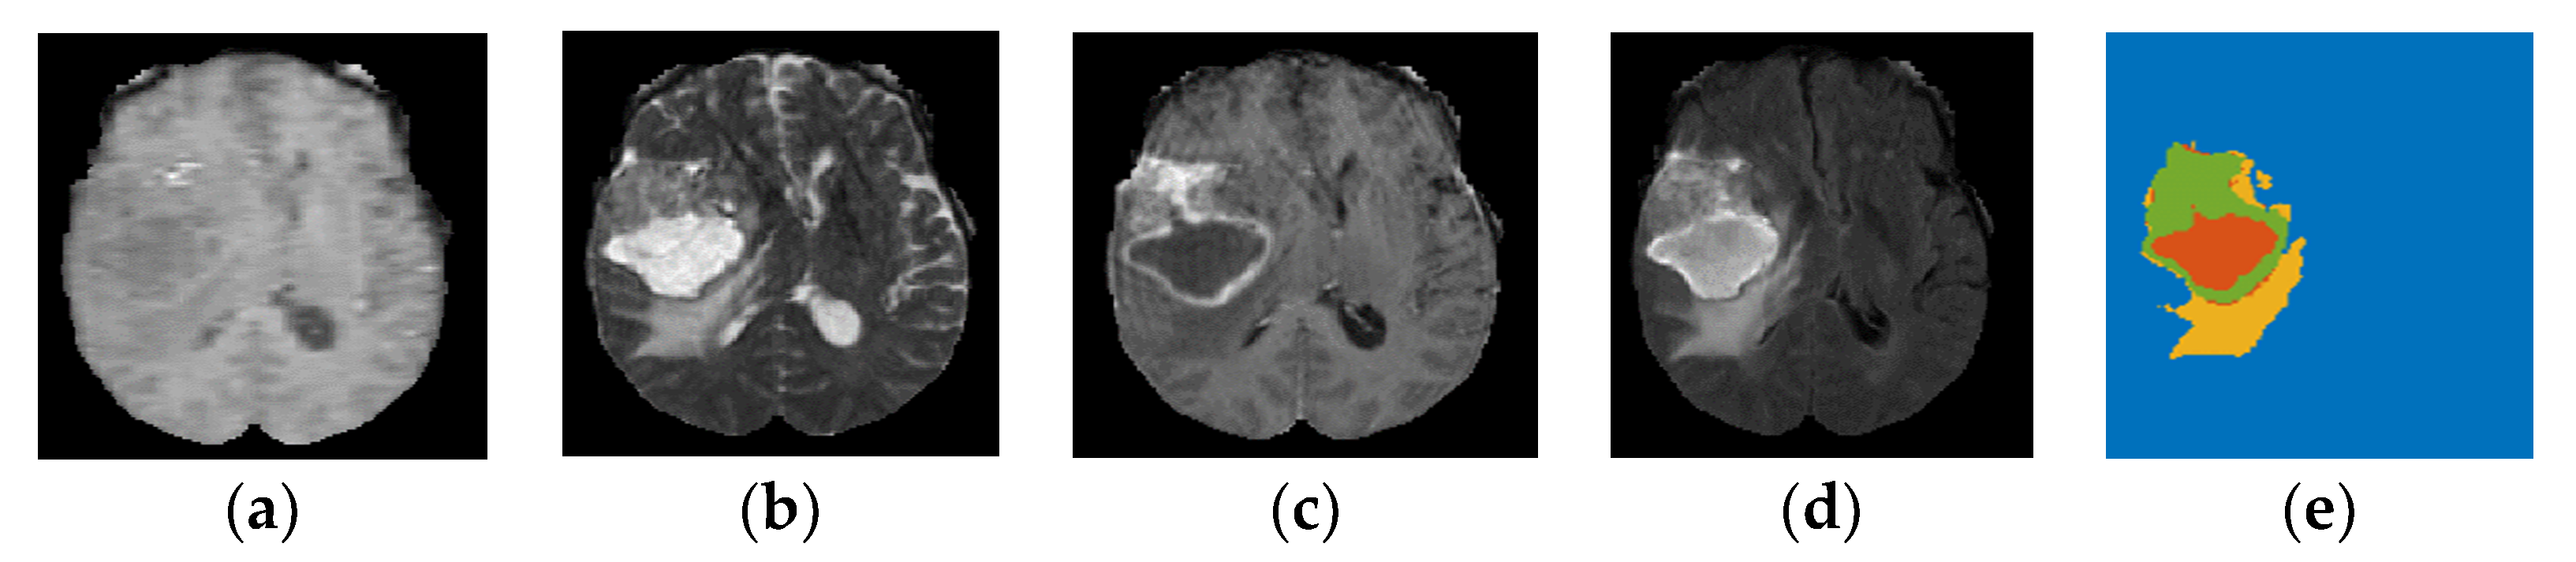

BraTS 2019 released well-processed medical data to segment glioma brain tumors automatically from medical images for HGG and LGG patients, as well as to predict the OST for HGG patients [23,29]. These medical data consist of medical imaging data and non-imaging data. As presented in Section 1, different modalities are used to accurately visualize each brain tumor subregion. Thus, the BraTS challenge provided four MRI scans (T1, T2, gadolinium contrast T1 (T1 Gd), and FLAIR) for each HGG and LGG patient, as they used them to annotate brain tumor subregions. The non-imaging data contained the patient’s age in years, survival time in days, and resection status for HGG patients only. These data contained three categories of resection status: gross total resection (GTR), subtotal resection (STR), and unknown resection status. The BraTS challenge provided a labeled imaging training dataset by professional radiologists for segmenting glioma subregions. The medical imaging data constituted 335 samples (i.e., patients), and each sample had 3D multimodal MRI scans with a segmentation labels file. Each MRI scan and segmentation file consisted of 155 slices, and the size of each slice was 240 × 240 pixels. The HGG group consisted of 212 samples (patients), with each sample having non-imaging data, as well as medical imaging data. The segmentation labels file consisted of four labels, each representing a specific brain tumor subregion, as well as heathy brain tissues and an image background: Label 1 represents the necrotic and non-enhancing tumor core (NCR/NET) region; Label 2 represents the ED region; Label 4 represents the ET region; Label 0 represents the healthy brain tissues and the background of an MRI image. Figure 2 shows the four MRI modalities with segmentation labels. Detailed information about the survival data is listed in Table 2. The distribution of the patients’ age with respect to the overall survival time of the three survival groups is shown in Figure 3a, and the boxplot of the patients’ age for each survival group is shown in Figure 4.

Figure 2. Multimodal MRI images based on 2D representation with segmentation labels (yellow: Ed, green: ET, red: NCR/NET) for a sample from the BraTS 2019 dataset-HGG group. (a) T1; (b) T2; (c) T1 Gd; (d) FLAIR; (e) labels.